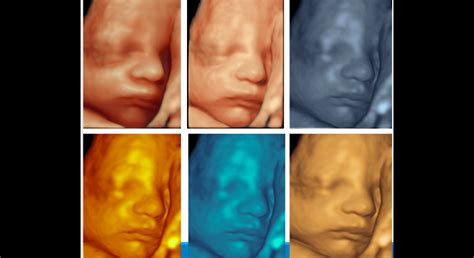

Okrem štandardného 2D ultrazvuku, ktorý poskytuje dvojrozmerný obraz, existujú aj pokročilejšie techniky ako 3D a 4D ultrazvuk. 3D ultrazvuk predstavuje statické zobrazenie plodu v priestore, pričom trojrozmerný obraz sa dosahuje počítačovým spracovaním súboru nakumulovaných 2D obrazov. Táto technika umožňuje získať detailné fotografie vášho bábätka.

Výukový program 4D ultrazvuku: Pochopenie 4D zobrazovania

Ďalšou možnosťou je 4D zobrazenie, ktoré sa od plastického 3D obrazu líši pridaním dimenzie času v podobe pohybu. Snímku vidíte v priamom prenose, môžete sledovať, ako sa dieťa hýbe, zíva, či dokonca naťahuje. Táto technika umožňuje vidieť dieťa v reálnom čase a sledovať jeho mimiku. Aj keď 3D ultrazvuk nie je vždy úplne zreteľný a "vydarený", je medzi budúcimi mamami pomerne obľúbený, pretože poskytuje krásne spomienky a detailný pohľad na dieťatko. Lekár vám môže z takéhoto vyšetrenia dokonca vytlačiť 3D fotografiu dieťatka.